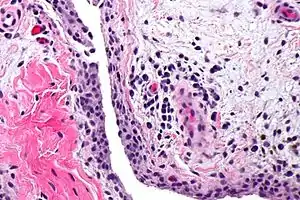

Synovitis

Synovitis is the medical term for inflammation of the synovial membrane. This membrane lines joints that possess cavities, known as synovial joints. The condition is usually painful, particularly when the joint is moved. The joint usually swells due to synovial fluid collection.

| Chronic synovitis | |

Synovitis may occur in association with arthritis as well as lupus, gout, and other conditions. Synovitis is more commonly found in rheumatoid arthritis than in other forms of arthritis, and can thus serve as a distinguishing factor, although it is also present in many joints affected with osteoarthritis.[1][2] In rheumatoid arthritis, the fibroblast-like synoviocytes, highly specialized mesenchymal cells found in the synovial membrane, play an active and prominent role in the synovitis.[3] Long term occurrence of synovitis can result in degeneration of the joint.